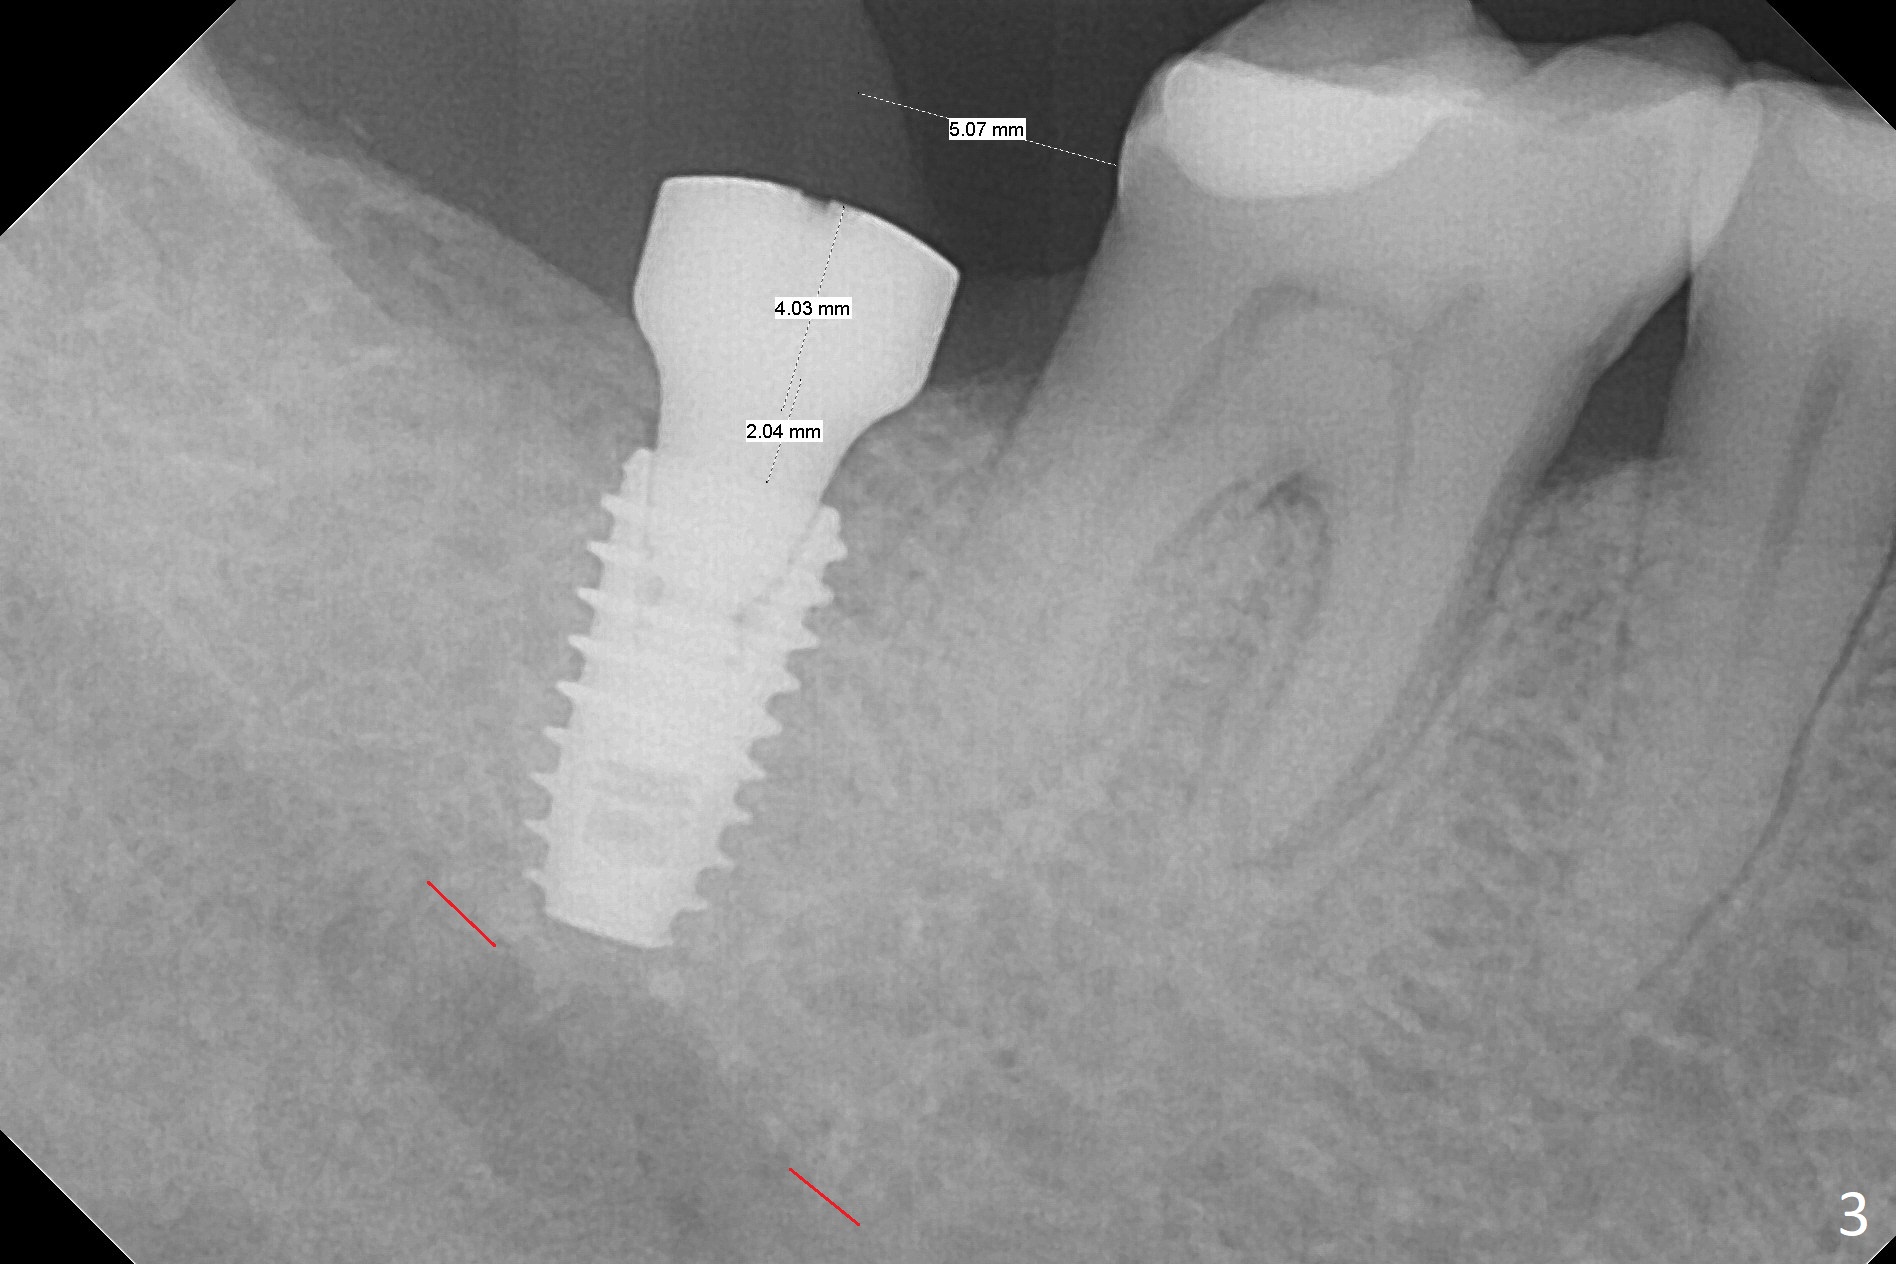

The ridge at #31 is wide buccolingually, but uneven with buccal lower. When a 3 mm drill reaches 13 mm in depth (Fig.1 (gingival level, flapless with Magic Split)), the patient feels pain with the osteotomy close to the Inferior Alveolar Canal (red dashed line). Subsequent osteotomy depth gradually reduces to 11.5 and 10.0 mm before placing a 4.5x8.5 mm implant initially with high torque. After rewinding, the implant is placed deeper (Fig.3 (implant plateau being even with the buccal crest)); a 5.5x4(2) mm healing abutment is placed due to severe supraeruption of the tooth #2. The patient refuses orthodontic intrusion. A prepped 5.5x4(2) mm cemented abutment is placed 6.5 months postop (Fig.3). After reduction of the lingual cusp of the tooth #2 (barely clearance), a provisional is fabricated at #31 to intrude the opposing tooth.